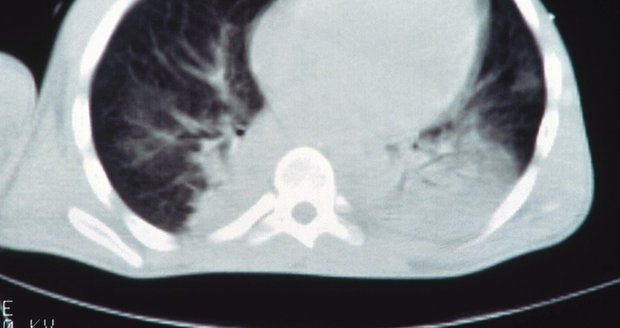

Pokud bakterie pneumokoka proniknou do částí těla, kde se běžně nenachází, mohou způsobit invazivní onemocnění – například zánět mozkových blan nebo otravu krve. Mezi neinvazivní nemoci pak patří zánět středního ucha nebo dutin. Jednou z nejčastějších forem pneumokokové infekce je zápal plic, který může mít jak invazivní, tak neinvazivní formu.

Při těžkém zápalu plic může dojít k poškození orgánu a pacienti se pak potýkají s dechovými obtížemi, sníženou fyzickou výkonností a jsou náchylnější k opakovaným infekcím plic. Pneumokokům se přitom téměř nelze vyhnout – přenáší se kapénkami při kašli, kýchání, mluvení a blízkém kontaktu. Vážná onemocnění hrozí především dětem, seniorům a chronicky nemocným pacientům.